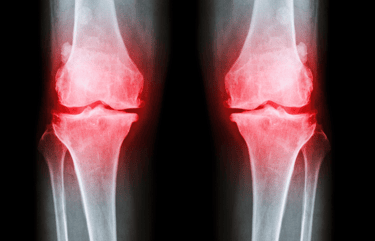

OA, the most common form of arthritis, affects millions of lives, causing pain, stiffness, and limiting joint motion.

However, people with OA may still experience symptom flares in the knee joints due to running.

OA may also affect areas of the foot and ankle. For example, OA can affect the joint in the first toe, which can cause push-off and a person’s gait to be painful.